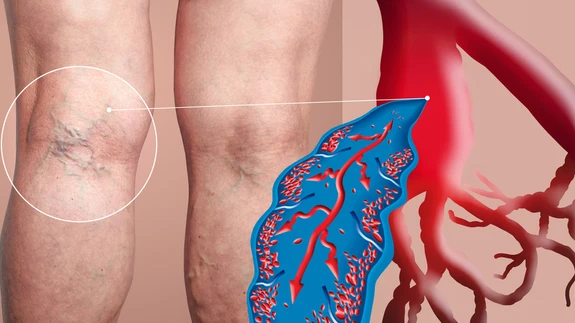

Kuumus ajab jalad paiste

Suvi toob sooja ja rõõmu, ent paljudele ka väiksemal või suuremal määral tervisemuresid. Enamikule meist on tuttav tunne see, kui kuuma ilmaga jalad paiste lähevad....

Miks jalad tursuvad?

Jalats ei taha jalga mahtuda või jätab sokk pahkluu kohale jäljed?...